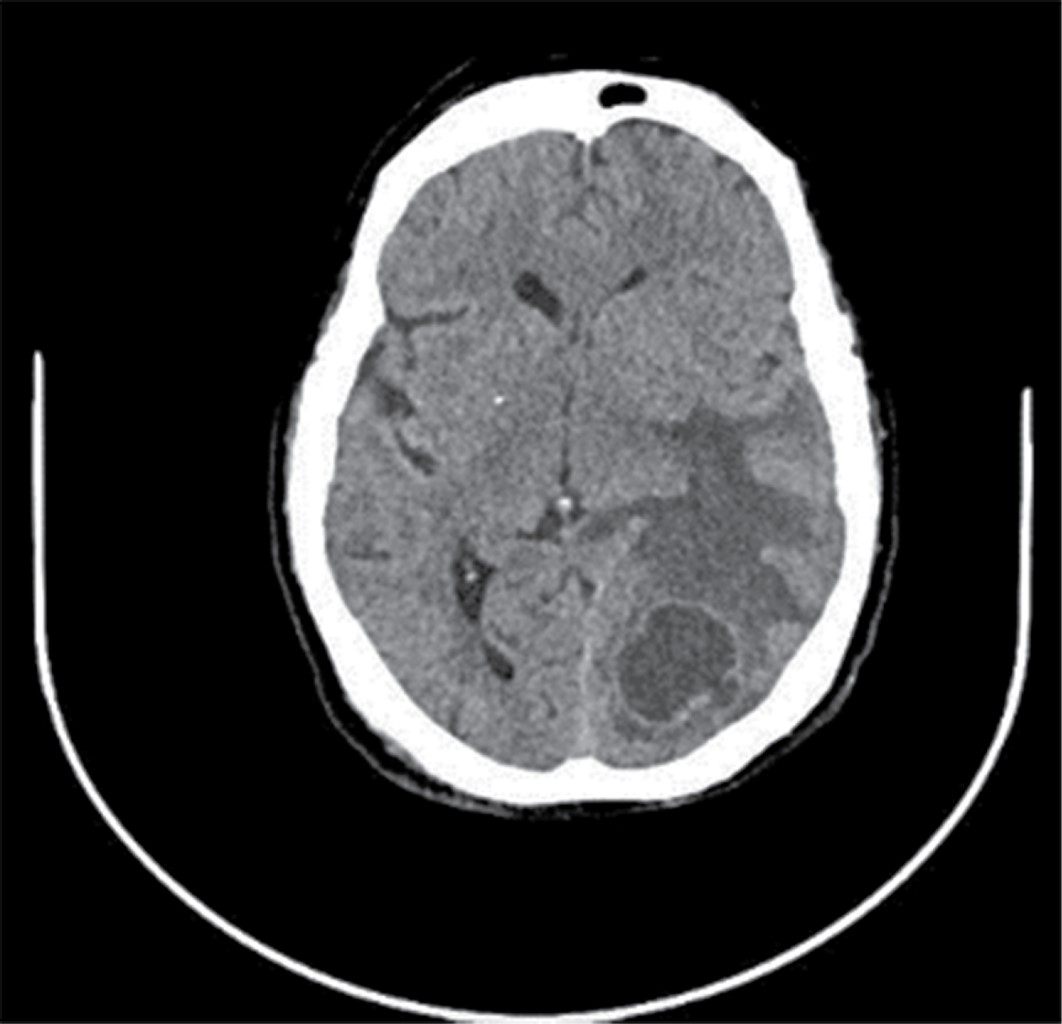

Extrapulmonary tuberculosis ''The great simulator''.

Tuberculosis is an infectious disease considered a public health problem since it is one of the main causes of morbidity and mortality worldwide; the most common clinical form is pulmonary tuberculosis; however, this disease can also affect extrapulmonary structures whose diagnosis is generally late because the symptoms and signs are nonspecific. This article presents a clinical case of extrapulmonary tuberculosis (miliary, central nervous system and intestinal) at the University Hospital of Puebla.

Figure 1